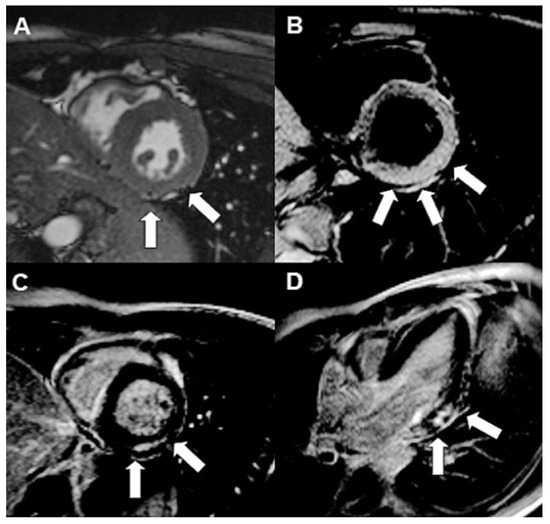

A patient with Morbus Behçet was admitted with severe symptomatic aortic regurgitation caused by aortitis that mimicked infective endocarditis. After aortic valve replacement and antibiotic treatment, regurgitation and systemic inflammation recurred....